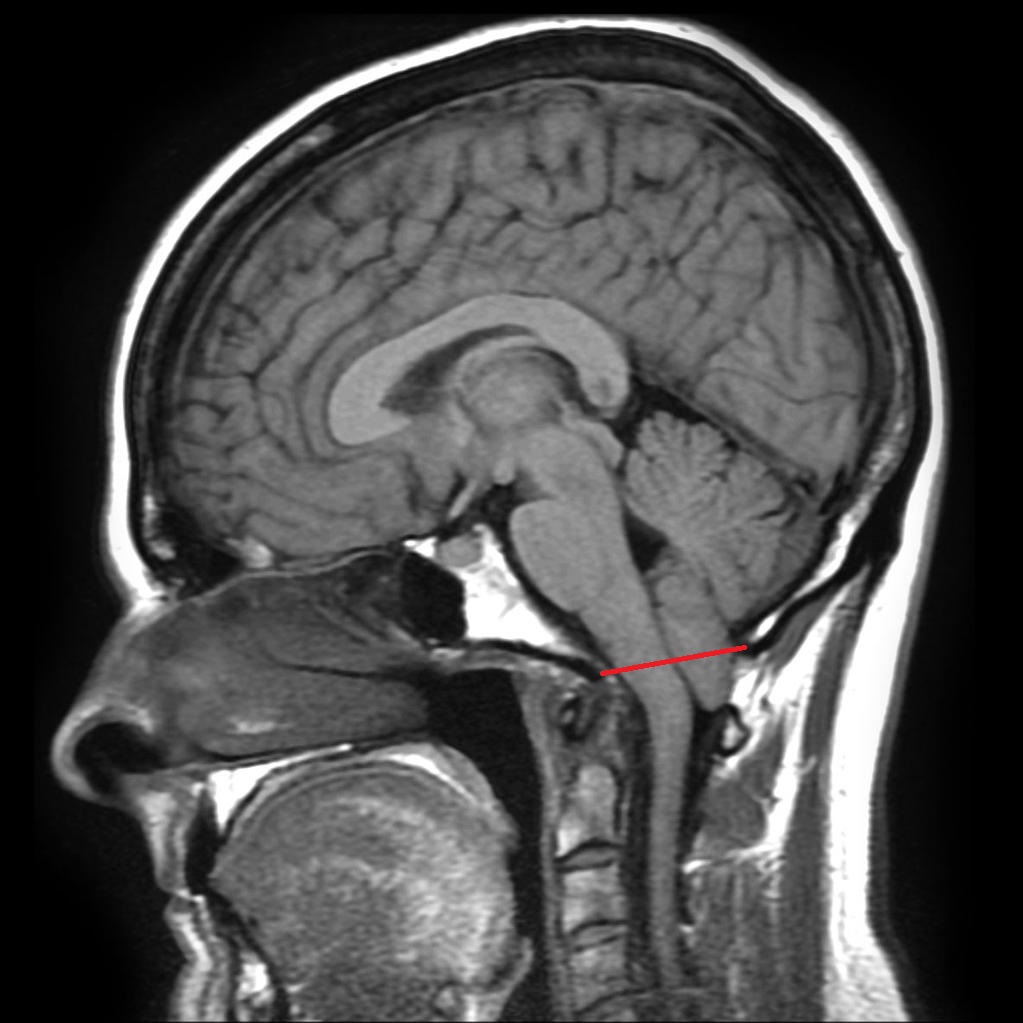

Ligne de McRae : du bord inférieur du clivus au bord inférieur de l’écaille occipitale